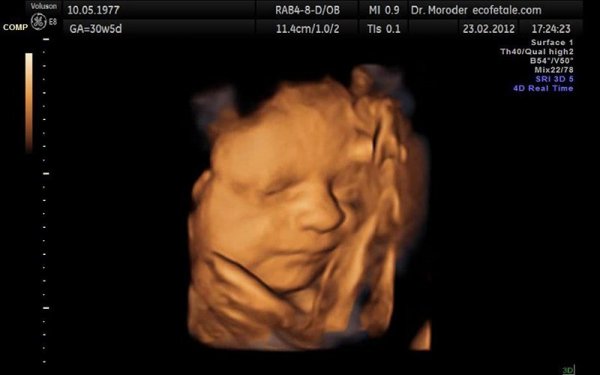

Ở giai đoạn tuần thứ 11 đến 13 này là các giai đoạn khám thai mà người mẹ sẽ được siêu âm 4D để kiểm tra hình thái của thai nhi nằm trong bụng. Lần siêu âm này là để kiểm tra vị trí của thai nhi đang nằm ngoài hay trong cổ tử cung, người mẹ sẽ được biết về số lượng thai là một hay song thai, thai nhi có phát triển bình thường không và dự đoán ngày sinh của em bé.

Khám thai lần thứ hai là một trong các tuần khám thai quan trọng vì siêu âm 4D có thể thấy được hình thái của thai nhi có ổn định không? (Ảnh: vinmec.com)